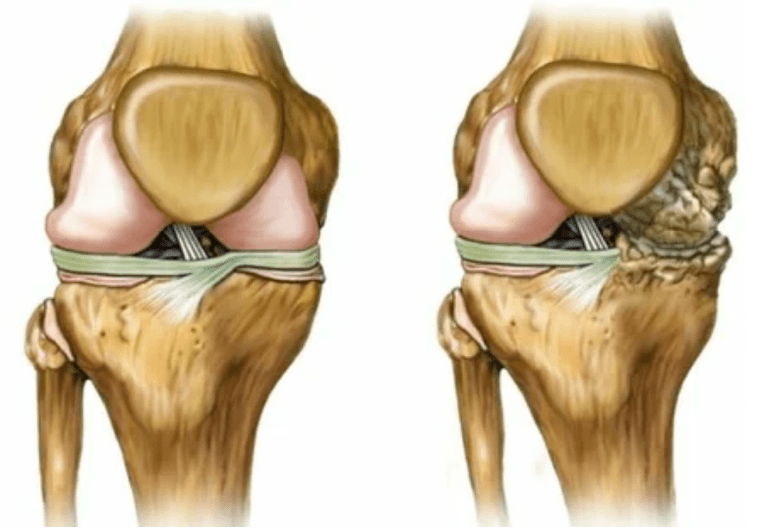

- Stage 2. Due to supply deficiency, the necessary cartridges are destroyed, bone growth is formed on the cartilage surface.The pains acquire a more pronounced character, intensified after a long break, are eliminated by a small physical work.The pain is accompanied by inflammation.The muscles stretch, which leads to weak or average motor functions.

- 3 degrees.There are often pain, it is difficult to move the limb due to changes in the joint.The lesions are extensive, they become notable to the naked appearance.The deformation of the joint site occurs, the affected area swells and becomes red.The axis of the limb is disturbed, which leads to the complexity of the movement.Pathological changes cause to shorten ligaments.Subuish and contractures appear.The adjacent muscles are shortened or stretched, of which the contractile function weakens.